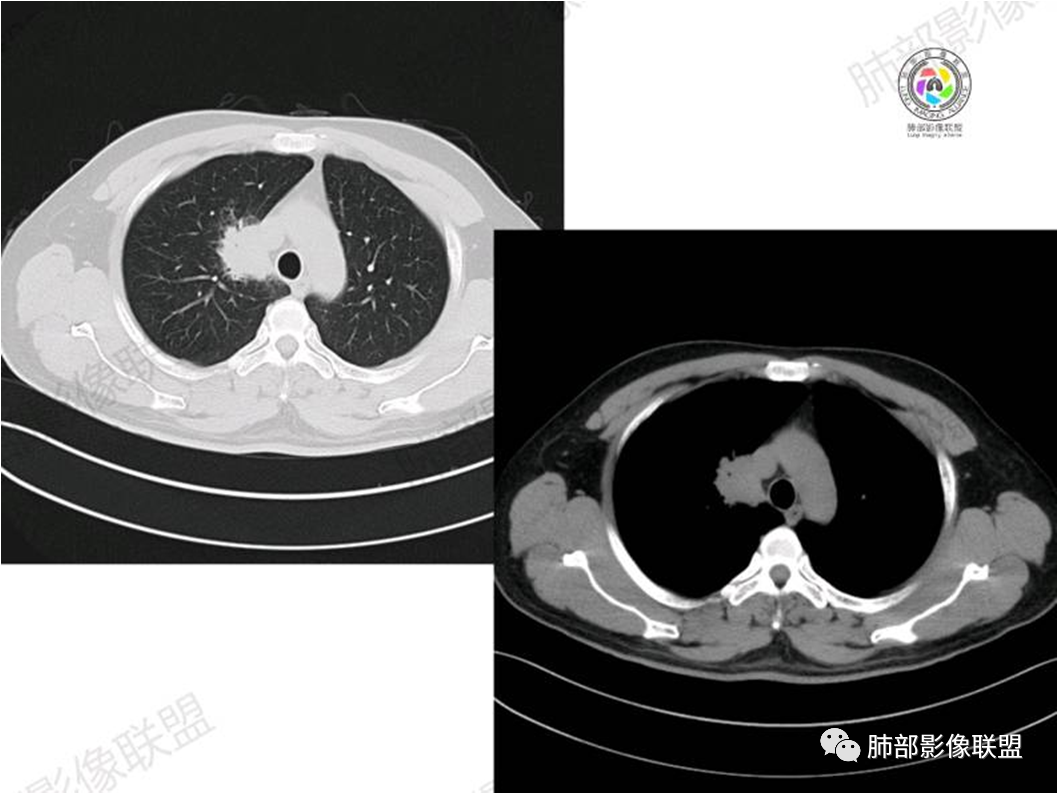

胸部CT:

中年男性,偶有咳嗽,右肺上叶近纵膈旁占位,内可见僵硬的支气管和小空泡征,病灶边缘可见分叶,毛刺,增强病灶中度以上不均匀强化,可见血管造影征,考虑恶性病变,腺癌可能性大。

中年男性,右肺上叶尖段团片病灶,密度均匀,内部支气管充气相,渐进狭窄,强化均匀,血管造影,纵隔侧未见侵犯,诊断:良性,慢性非特异性炎症/机化性炎症,IMT

右肺上叶纵隔胸膜侧一实性肿块,与纵隔胸膜宽基底相连,局部脂肪间隙消失,形态欠规则,内部可见多个小空泡,平扫密度尚均匀,增强后可见点条状强化,内部穿行血管,周围肺组织干净,纵隔淋巴结略肿大,男性44岁,只有咳嗽,考虑恶性肿瘤,腺癌,鳞癌。鉴别结核,OP,炎性假瘤。

右肺上叶近纵膈旁肿块,密度均匀,边缘分叶,毛刺,气管受压变窄,不均匀强化,可见血管造影征,考虑淋巴瘤,鉴别炎性假瘤。

中年男性,右肺上叶纵隔旁软组织肿块,边缘膨隆、毛糙,可见多发分叶,支气管穿行,部分截断,增强后密度欠均匀,纵隔内见多发小淋巴结,首先考虑恶性,腺癌,鉴别淋巴瘤

中年男性,右肺上叶纵隔旁肿瘤,稍膨隆,有毛刺,支气管穿行,远端闭塞,强化均匀,血管走行尚可,考虑淋巴瘤可能性大(支气管远端闭塞,不太符合),鉴别腺癌(气管穿行后闭塞,不太符合),op(病灶稍膨隆)

患者中年男性,咳嗽就诊,无其他不适。胸部CT:右肺上叶尖段上纵膈旁肿块,边界清楚,边缘光滑,内见支气管受压变窄,伴阻塞性改变,增强均匀强化,见血管造影征。综合考虑恶性病变,小细胞肺癌或淋巴瘤。气管镜活检应能明确。

中年男性,右肺上叶纵隔旁实性病灶,边缘有彭隆,有平直,有分叶,有尖角,病灶边缘中心可见支气管征,周围少许磨玻璃,边缘模糊,增强后动脉期病灶可见强化血管影,渐进性强化,临近血管界限清晰。考虑炎性病灶,普通炎性肉芽肿?结核?炎性肌纤维母细胞瘤?鉴别腺癌,淋巴瘤